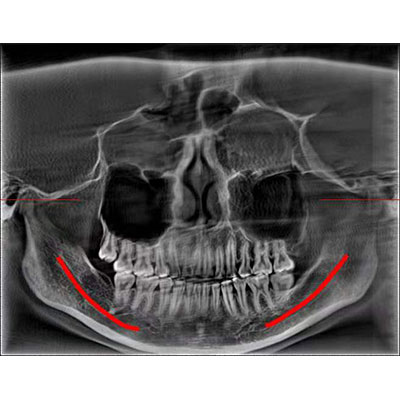

高清口腔三維CT/全景影像 PLX3000A

該款牙科CBCT產(chǎn)品采用動態(tài)平板探測器,獲得三維圖像的同時還具有數(shù)字化全景功能,廣泛應用于口腔頜面外科、正畸科、正頜外科、種植科、牙體科、顳下頜關(guān)節(jié)科等術(shù)前術(shù)后。

通過三維容積影像,提取高清口腔全景影像。